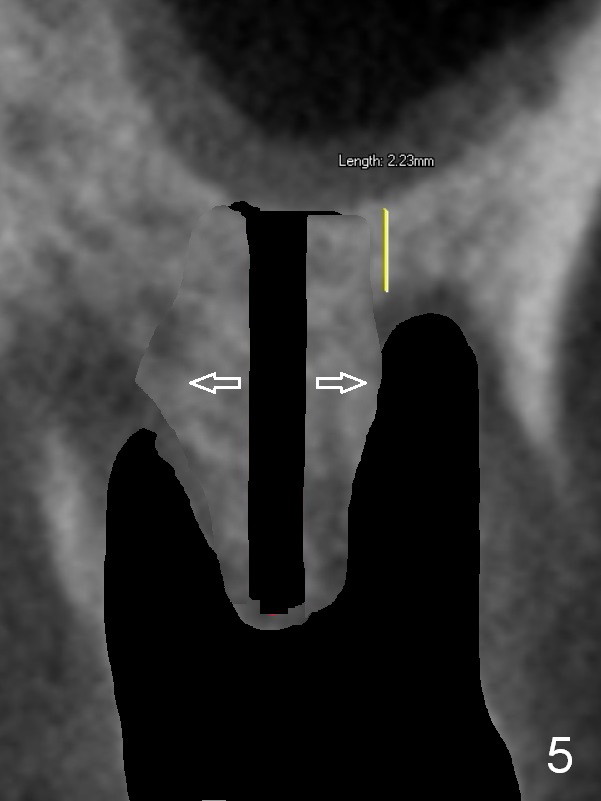

Preop CT shows that the septum appears to be able to hold a 11 mm long implant (Fig.1 sagittal section). There are periapical radiolucent lesions of the buccal (Fig.2 (coronal section) B) and palatal roots; bone height above the buccal apex is ~ 2 mm (Fig.3). When the tooth #14 is extracted, a 1.6 mm pilot drill is used to start osteotomy in the middle of the fairly thin septum (Fig.3 red line, Fig.4 S). It is hoped that Magic Expanders (ME) can enlarge the osteotomy by pushing the buccal and palatal bone plates of the septum outward (Fig.5 arrows).

The septal bone is dense and the osteotomy is enlarged by alternating use of drills and expanders. By the time 3.8 mm ME is tapped in (Fig.6), the buccal plate of the septum is perforated. The ME is stable, in spite of the fact that it is only supported by 2-3 mm bone buccally (Fig.7). Continuously alternating use of MEs and drills leads to placement of a 5x11 mm implant with 30 Ncm insertion torque and sinus lift. After placement of bone graft (Fig.8 *) and 5x4(3) mm pair abutment (A), an immediate provisional is fabricated. Red dashed lines in Fig.6,9 represent the mesial outline of the socket, whereas black dashed in Fig.6 sinus floor. It suggests that the implant is stabilized by relatively small amount of native bone. Although IBS implants have aggressive thread patterns, a proper apical osteotomy should be prepared in the depth (perforates the sinus floor in this case) and diameter (4.3 mm drill) prior to placement.